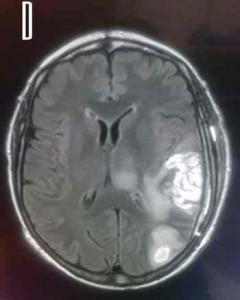

Glioblastoma multiforme

Es el tumor más común y más maligno

entre las neoplasias de la glía. Puede manifestarse a cualquier edad,

pero afecta principalmente a adultos, con un pico de incidencia entre

los 45 y los 70 años. Se presenta habitualmente en los hemisferios

cerebrales, siendo menos frecuente su localización en el tronco del

encéfalo o la médula espinal.